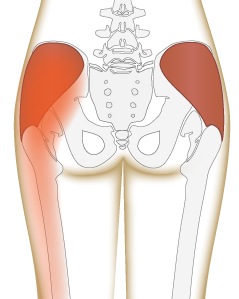

·原因: 疼痛大约在屁股摺痕处。尤其是在你膝盖伸直且将身体向前弯腰时,症状会更明显。这种型态的疼痛表示是连接到骨盆的腘绳肌肌腱受伤,这通常是因为过度的拉扯腘绳肌。(如在瑜伽中:当瑜伽练习者需要保持双腿笔直向前弯曲,然后强迫自己摆姿势时,可能最终会损伤肌腱。)当我们的肌腱受伤,腘绳肌会自然的收缩,试图去保护受伤的肌腱。然而我们认为的是:"腘绳肌紧绷又疼痛,要去伸展它,疼痛自然会消失了",而这样的方式却无法让肌腱修复,反而是重复使其受伤——过度伸展然后再受伤,这样的循环会使复原时间变更长。较好的方式是借由适当地收缩腘绳肌来增加受伤区域的循环,如果可以的话,做简单轻微的伸展。当疼痛急性期结束后,你可以慢慢增加伸展的角度。您的朋友或患者中,是否有人向你这样抱怨过:我的髋部在走路、睡觉时会痛,物理治疗师建议他作核心运动,骨科医师诊断他是梨状肌症候群,也试过请按摩师放松他紧绷的髂胫束。经过仔细的检查后,确认了他疼痛的位置,疼痛的症状都指向无力的外展肌群,造成骨盆位置不良,导致某些肌肉群去代偿。当开始训练他的外展肌群,很快地他的疼痛就不见了。此型态的疼痛通常会出现在臀部外侧或上侧,可能会向下至大腿的外侧。它通常是在散步跟晚上侧躺在患侧时更糟。薄弱的外展肌群,紧绷的髂胫束可能是引起疼痛的一种因素。这种疼痛常被认为是髂胫束的问题,所以借由伸展髂胫束,或用滚筒去放松,这会非常有效,但并没有解决问题的根源-外展肌无力,除非你去加强肌力,否则问题会一再出现。你需要锻炼你的髋外展肌,可以利用单脚站,另一侧大腿对抗重力做髋外展动作,两侧轮流施行,让髋外展肌做为稳定以及动作的功能角色。大家知道坐骨神经分布的范围到底有多大吗?它是你的身体里最长的一条神经,从下段脊椎一路延伸到脚,而且它也非常的粗,大概就像是你的小指头一样粗,穿过你的脊椎与髋关节。因为这条神经粗又长,它可能在很多地方被挤压到,而造成类似坐骨神经痛的症状。两个常见被挤压位置在下背部(腰椎椎体间)跟紧绷的梨状肌下面。梨状肌是一条很小的肌肉,当它太紧绷时可能会造成很多困扰。它位于髋部深处,在髋关节弯曲状态下,负责带动髋关节外转跟外展。紧绷的梨状肌会造成屁股痛,但当它压迫到通过梨状肌下面的坐骨神经时,就会使情况变得更糟。疼痛通常会出现在臀部中间的位置、下背部,或任何坐骨神经通过的地方。症状也有可能是脚麻或无力。如果是因为椎间盘突出引起的坐骨神经痛,是比较大的问题,超过我们本篇所要介绍的范围,在物理治疗师的指导下,加强核心肌群的运动是个不错的方式。如果疼痛是因为紧绷的梨状肌,我们可以着手于放松紧绷的肌肉。·较好的方式:利用我们常见的”收缩-放松-伸展原则”(Contract-Relax-Stretch principle)步骤①:从收缩周围肌肉开始(尤其是臀大肌),来增加此区域的血液循环。步骤②:然后我们可以轻轻的收缩梨状肌 (contract the piriformis ),让它慢慢放松掉原本慢性的收缩(如果不会感到疼痛),搭配温和的伸展。我们可以借鉴瑜伽中的动作,像是勇者式二(Virabhadrasana 2)、侧三角伸展式(Utthita Parsvakonasana)跟蚌蛤式都可以让梨状肌收缩,而在站姿下利用椅子做扭转动作,以及半鱼王式(Ardha Matsyendrasana)是伸展梨状肌最好的选择,因为此姿势会让你的脚处于弯曲、内收,但不会外转的姿势,这对于梨状肌是比较温和的姿势。步骤③:当你觉得你已经准备好在伸展加入外转的动作时,你可以选择穿针引线式(Thread-the-needle pose)来取代鸽式(Pigeon)或牛面式(Gomukasana),这会让使梨状肌受到较小的力矩。当你练习这些动作后,你就可以试着做鸽式(Pigeon)或牛面式(Gomukasana)。PS:但有些学生即使练习很久也还是没办法完成鸽式或牛面式。此外,由于过紧的内收肌群会使髋关节呈现内转姿势,使梨状肌产生额外的压力进而压迫到神经,所以也可使用相同的方式来舒缓内收肌群的慢性紧缩。紧绷的腘绳肌也会造成坐骨神经受压迫,所以对于缓解此肌群的张力也是很有效果的。请记住,即使最简易的腘绳肌伸展运动也可能造成一位有坐骨神经痛症状的人极大地疼痛,所以建议用前面提及到第一种臀部疼痛的腘绳肌伸展原则。 请记住,一个疼痛症状,有可能是许多原因造成的。如果您的疼痛在你经过一番努力后,仍然存在,应该是要去寻求专业建议的时候了。